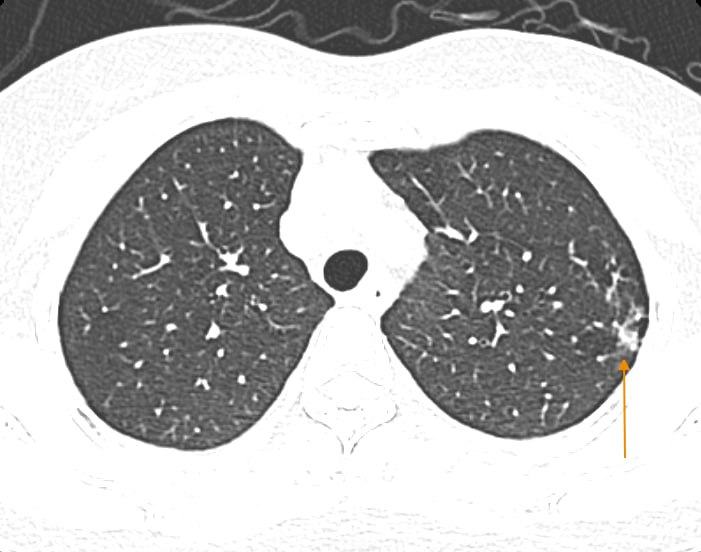

09/02/2025 01:05Mắc cúm A, người phụ nữ Hà Nội phổi như bị bóp nghẹt, 'không thể thở nổi'

Bệnh nhân P.T.H. (51 tuổi, Hà Nội) ở nhà có triệu chứng ho nhiều, ho có đờm, đau rát họng kèm người gai rét, sốt cao. Bệnh nhân còn xuất hiện thêm tình trạng đau rát vùng sau xương ức và khó thở.

Bệnh nhân nghĩ mắc cúm thông thường nên tự mua thuốc về uống. Tuy nhiên, tình trạng không thuyên giảm, vẫn tiếp tục sốt cao kèm mệt nhiều, ăn kém, khó thở, tưởng như phổi bị bóp nghẹt, "không thể thở nổi". Do đó, bệnh nhân đã quyết định nhập viện ngay trong đêm.

Tại Bệnh viện Đa khoa Medlatec, bệnh nhân được test có dương tính với cúm A. Hình ảnh chụp cắt lớp vi tính phổi độ phân giải cao cho thấy bệnh nhân gặp biến chứng viêm phổi. Hiện tại, bệnh nhân tiếp tục được điều trị và theo dõi tại khoa Nội.